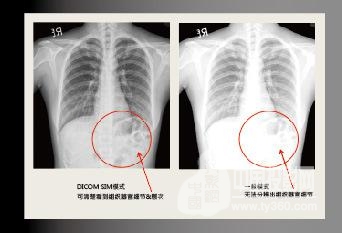

支持DICOM.SIM醫療設備模擬顯示模式

DICOM.SIM 顯示模式能夠使投影機模擬醫療設備的灰度/Gumma性能來顯示圖像,相對沒有沒有DICOM模式的投影機,可以更精準地表現灰階圖像,且清楚地傳達醫療訊息,有助于診斷&治療細節討論。 注:此模式僅用于教育培訓或會議討論,醫療診斷禁止使用!